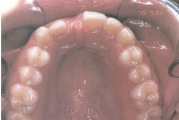

Ülemise hambakaare kitsenemine ehk tagumiste hammaste risthambumus.

ülemine hambakaar on alumisest laiem nõnda palju, et hambad kokku ei puutu